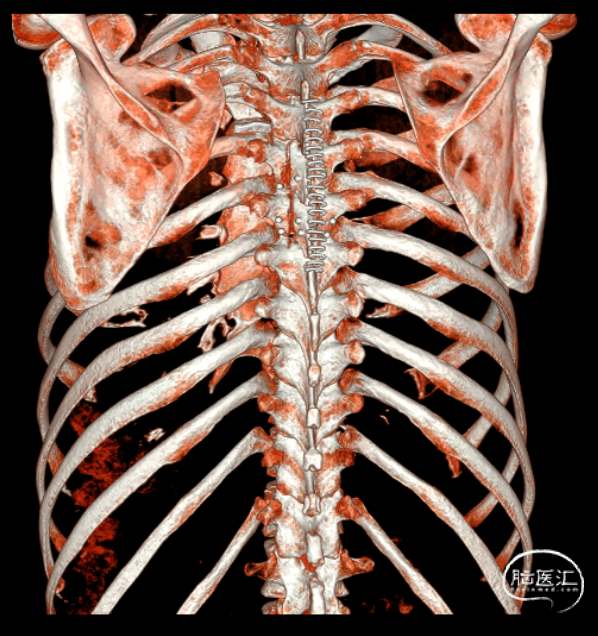

术前影像(2024-02-20, 本院)

image.png